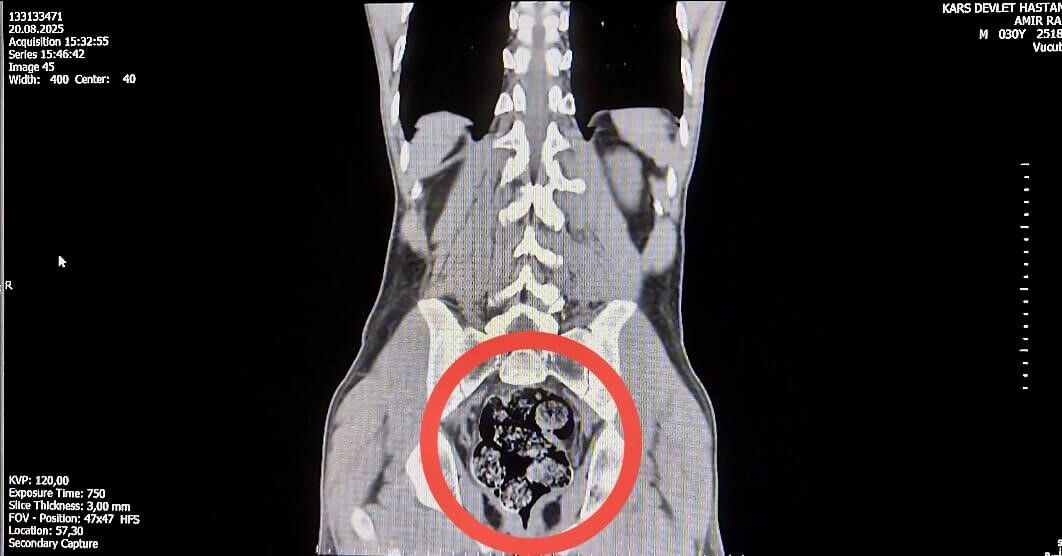

Düzenlenen operasyonda, İran uyruklu kuryeler gözaltına alındı. İl Emniyet Müdürlüğü'ne getirilen ve durumundan şüphelenilen kuryelerden Shekarbaghanı, detaylı arama için Kars Harakani Devlet Hastanesi'ne götürüldü. Hastanede yapılan emar ve röntgen kontrollerinde şüphelinin makatında cisim olduğu belirlendi. Yapılan cerrahi müdahalede, şüphelinin makatından 7 parça halinde 203,02 gram metamfetamin çıkarıldı.